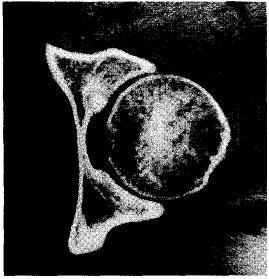

Рис. 20.3. КТ тазобедренного сустава. Хорошо видно ядрышко, расположенное в зоне субхондральной пластинки. Гистологическая дифференциальная диагностика с остеогенной саркомой проводится по всей сумме признаков, при этом электронная микроскопия не всегда играет большую роль. Даже после расширенных резекций наблюдаются местные рецидивы опухоли, возникающие в ближайшие месяцы. По литературным данным, возраст больных — от 6 лет до 71 года. K.Morimoto (1975) путем исследования ткани на микрорентгеноанализаторе показал, что соотношение Са и Р в костных кристаллах в остеосаркоме выше, чем в остеобластоме.

Рис. 20.3. КТ тазобедренного сустава. Хорошо видно ядрышко, расположенное в зоне субхондральной пластинки.